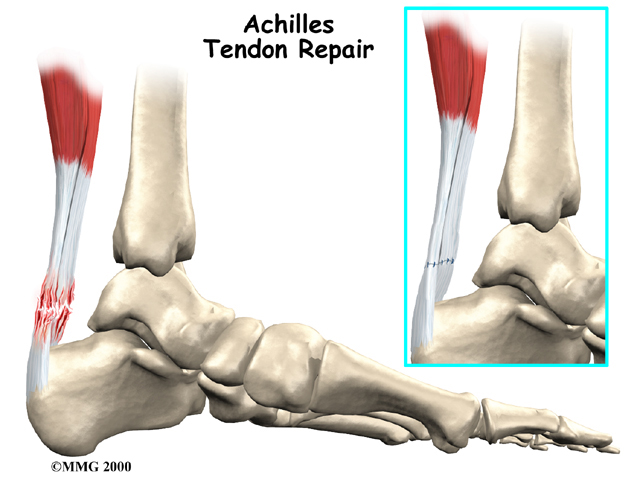

Achilles Tendonitis

The tendon sheath, the tissues of the tendon, and the attachment to the bone can all become injured in the:

Achilles Tendon

found in the lower leg. Damaged Achilles tendons carry a higher risk of rupturing because of the weight they bear while standing and walking.

Related Document: *client_company's Guide to Achilles Tendon Problems

The pain or swelling in your tendon may make your joint hard to move. Some types of tendon problems cause crepitus, a crackling feeling when the joint moves. In rare instances the weakened tendon may actually rupture, or break, with a sudden force. This may require surgery to repair.

Most people with chronic tendon problems can find ways to relieve the pain and take part in their normal activities, even if the problem doesn't completely go away. In a few cases, patients can't find ways to manage the pain even after six months. For these few patients, surgery may be necessary. Surgery may be successful in relieving the pain of chronic tendonitis.